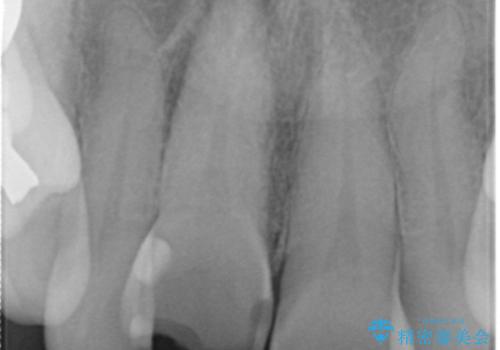

- 転んで前歯が折れたとのことで来院されました。

検査の結果、歯は大きく折れておらず、骨の中に埋め込まれていた状態であったため、部分矯正で歯を引っ張り出していきます。